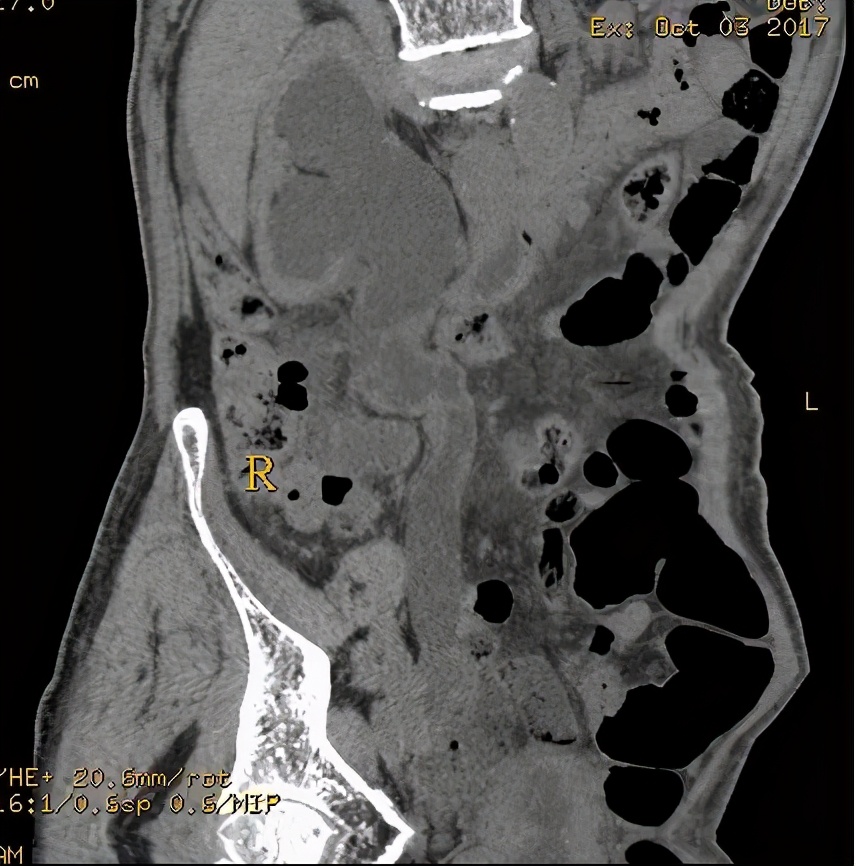

上图所示,(左侧)肾盂癌,压迫(左侧)输尿管上段。